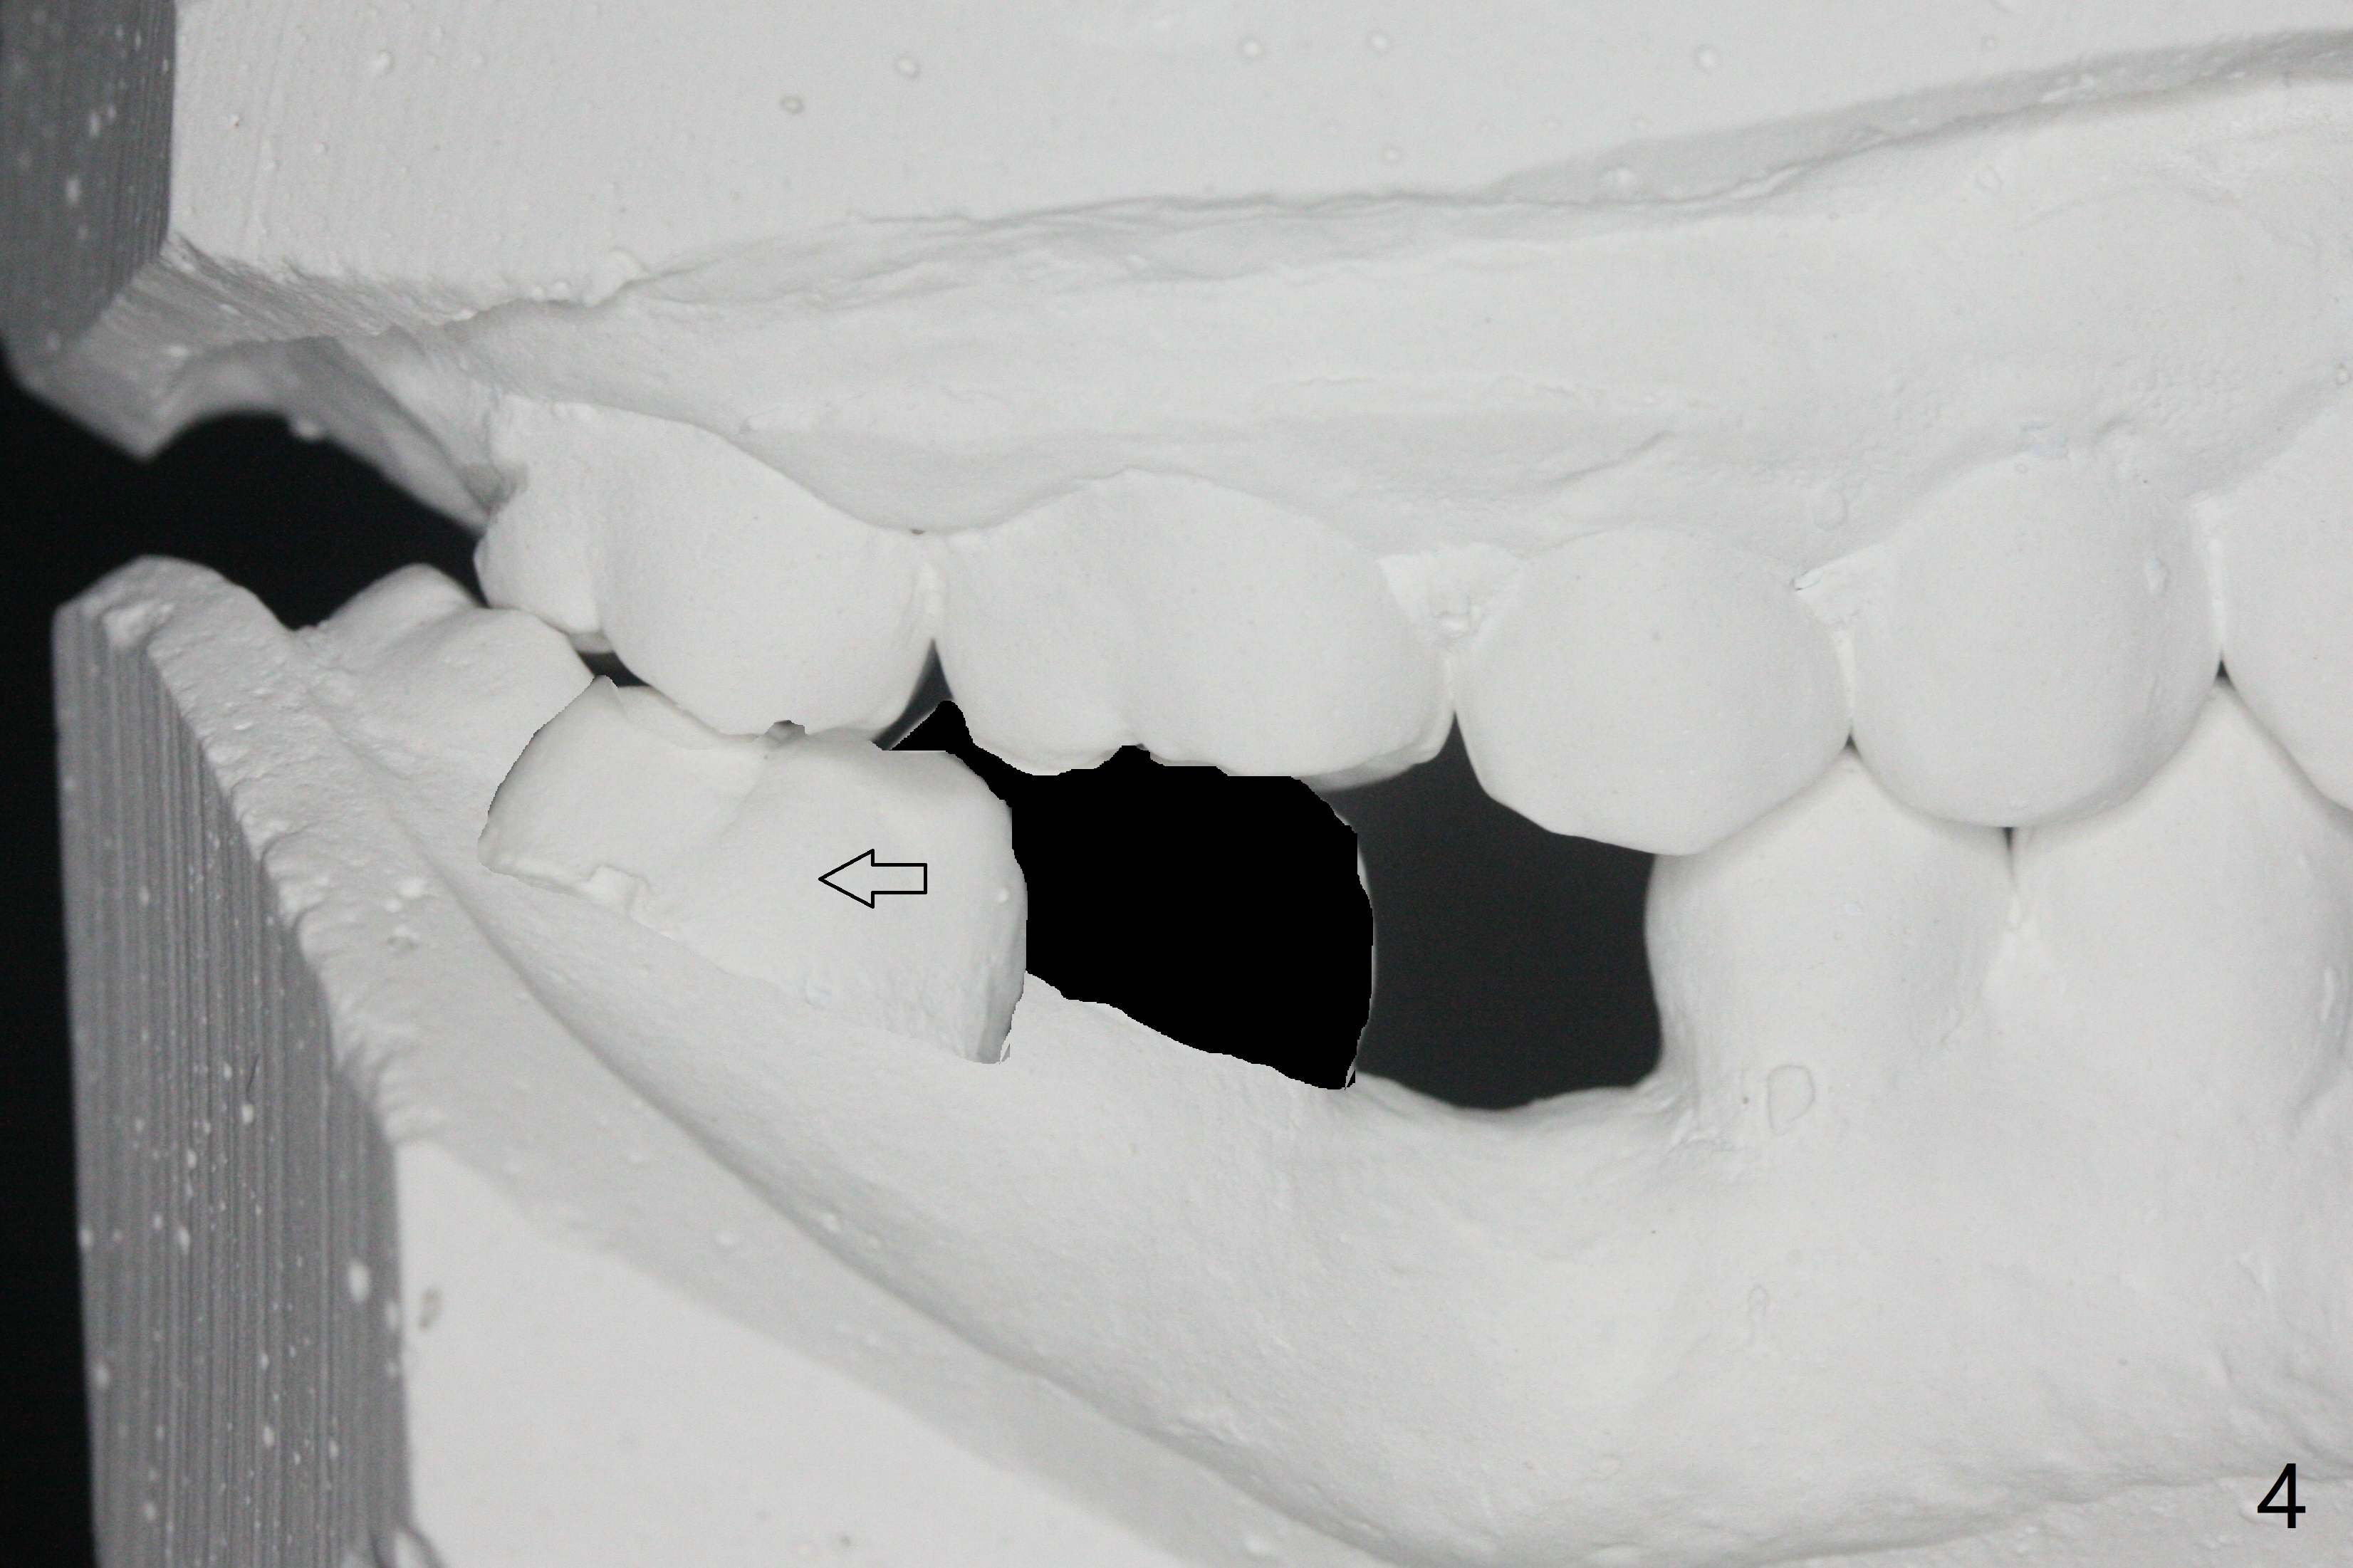

27岁女,小的时候在国内做过牙齿矫正,留下不好印象,不愿意再次矫正。她缺失右下6;7,8明显近中移位(图一,二)。左下7近中颊侧牙尖位于上6,7之间(图三:^),理论上,右下7必须远中移位到8牙位一半(图四)。经过反复讨论(包括前移7,8),病人同意拔除8,做右下后牙区矫正。为了有效7远中移位,拔除8后即刻种植(图五:绿色),植骨(红圆圈),覆盖PRF膜(紫色线)。一旦植牙整合,制作临时牙冠(图六:蓝色;并且提高咬合,这样7有垂直空间后移(直箭头)旋转(弯箭头)),永久性粘固,可能在7,8之间使用power chain,起牵拉作用,棕色方块代表矫正器。一旦6空间扩大,植牙。整合后也可以作为支抗,继续将7远中推移。一定时光,取出智齿植体,完成暂时性支抗作用。